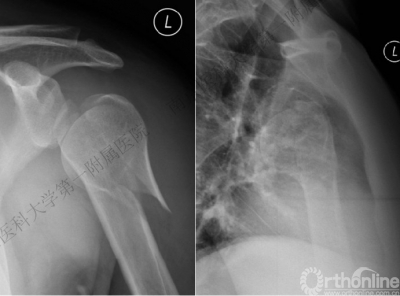

病例1

男性,40岁,摔伤后右肩关节肿痛、活动受限2天。

术后肩关节X线正位片

病例2

男性,48岁,坠落伤致左肩关节肿痛、活动受限1天。

病例1与病例2是同一类损伤吗?